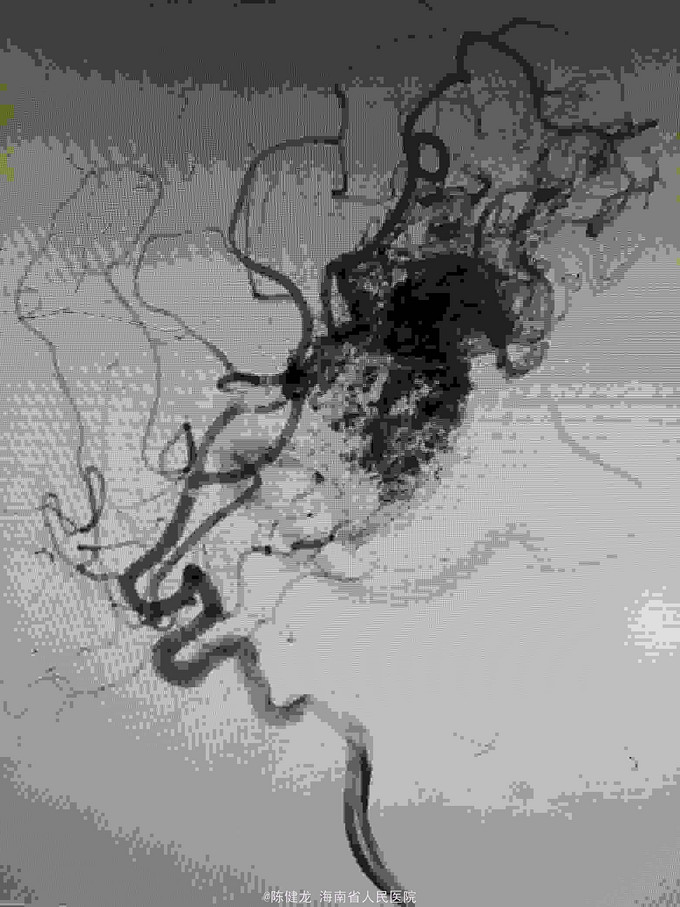

AVM

右颞大型AVM,大脑中主要供血。

右颞AVM

己进行二次治疗,拟近期内进行第三次治疗。争取80%至90%栓塞,残留部分伽玛刀治疗。